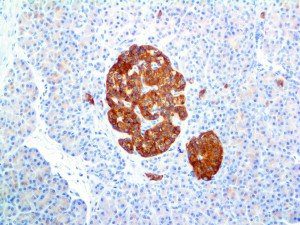

It is the ICU physician who is most likely to witness one of the deadliest manifestations of the abnormal immunological response, the cytokine storm syndrome (CSS). This response is also referred to by some as the cytokine release syndrome (CRS). CSS is characterized by continuous activation and expansion of macrophage and lymphocyte populations, which secrete large amounts of cytokines, causing the cytokine storm. This massive cytokine release is akin to hemophagocytic lymphohistiocytosis (HLH) disease, a syndrome characterized by initial unchecked and persistent activation of cytotoxic T lymphocytes and NK cells.

Clinical and laboratory manifestations of HLH include fever, enlarged liver and/or spleen, neurologic dysfunction, coagulopathy, liver dysfunction, cytopenias (i.e., low levels of erythrocytes, leukocytes, and/or platelets), hypertriglyceridemia, hyperferritinemia, hemophagocytosis, and eventually diminished NK cell activity as the immune system becomes progressively paralyzed. HLH can be familial (primary HLH) or secondary to another disease process (sHLH), such as rheumatic disease, in which it is referred to as macrophage activation syndrome (MAS, characterized by elevated ferritin).